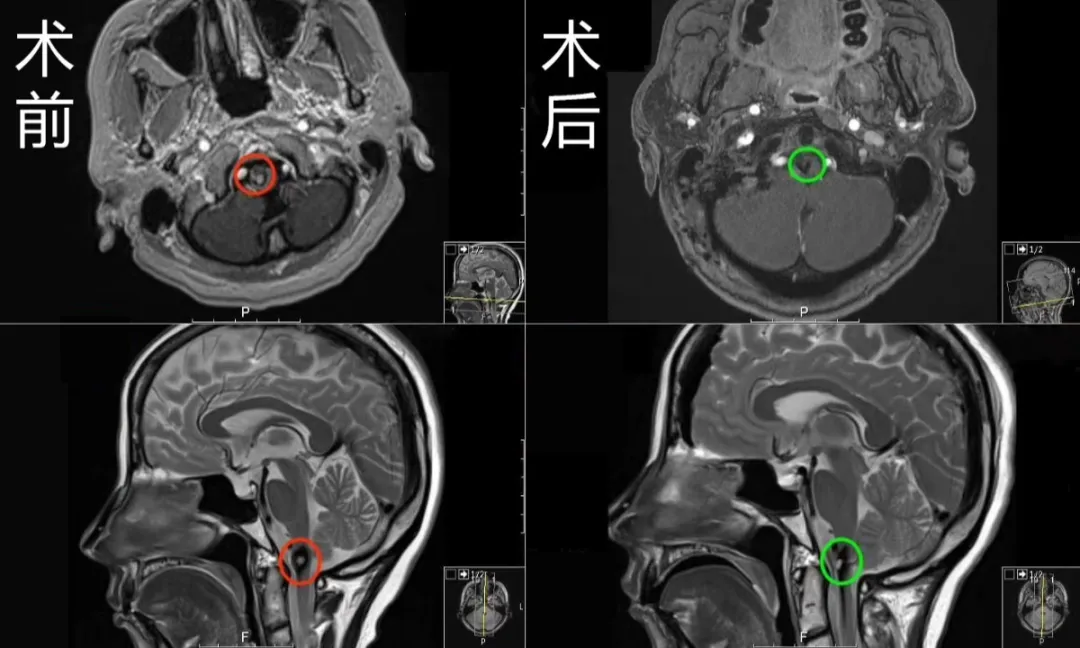

(术前术后MR对比)

术前MR显示:延颈髓偏右侧见一直径约1cm占位性病变,周围见环状含铁血黄素低信号影环绕,提示海绵状血管瘤。